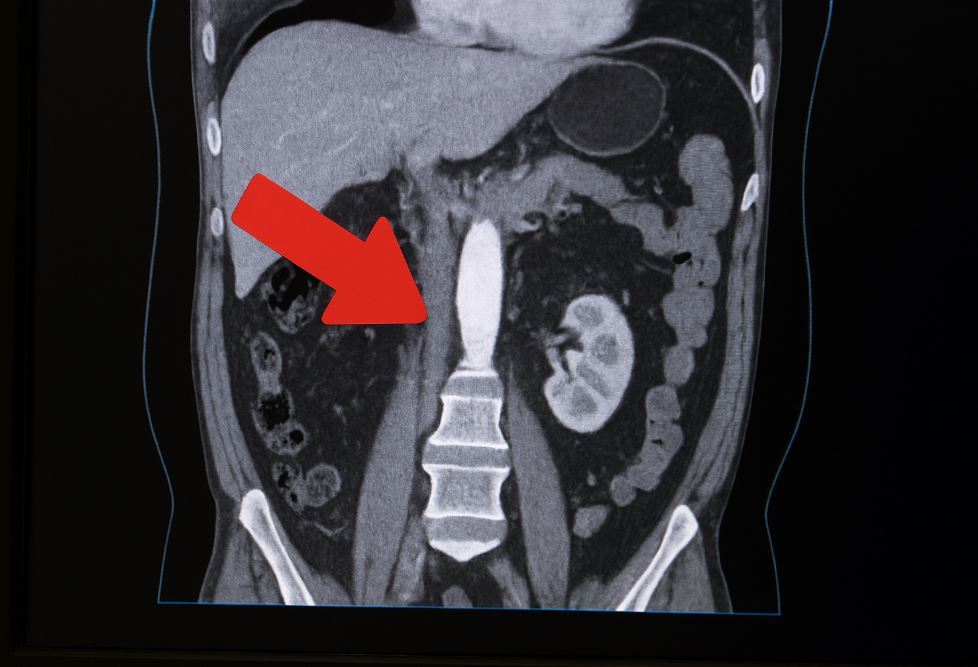

복부 대동맥류는 배 속의 가장 큰 혈관인 대동맥 일부가 약해지면서 풍선처럼 부풀어 오르는 질환이다.

최근 강동경희대학교병원 연구팀이 2010년부터 2022년까지 국민건강보험공단 자료를 분석한 결과, 복부 대동맥류 환자 수는 약 4000명에서 1만3000명으로 3배 이상 늘었다. 특히 파열되기 전에 발견된 ‘비파열 대동맥류’ 환자가 대부분이었으며, 같은 기간 크게 증가했다. 연구진은 인구 고령화가 주된 요인으로 작용했다고 분석했다.